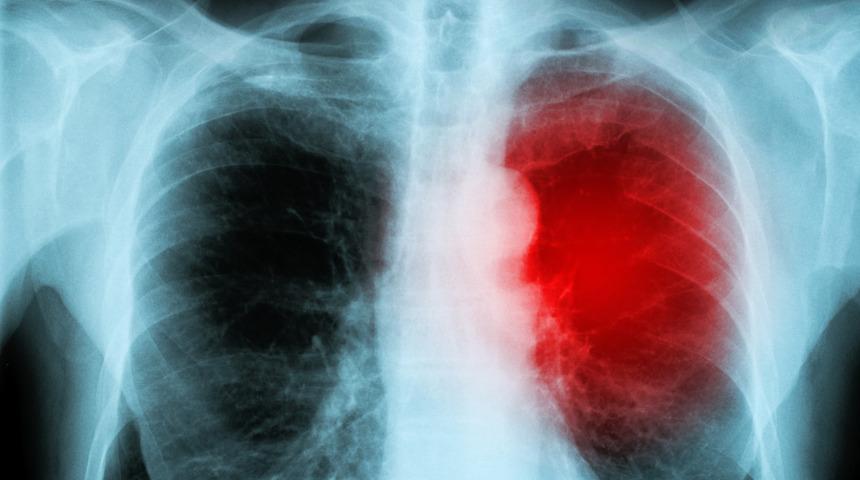

Miyokardit hastalığı belirtilerinin olduğu kadar teşhis için kullanılan yöntemler de tedavi açısından önem taşır. Belirtiler göz önüne alınarak kalp ritimlerini gözlemlemek için EKG ve Holter monitörü, kalp yetmezliğine sebep olan sıvıya bakmak için göğüs röntgeni, kalbin yapısını detaylı incelemek için MR ve enfeksiyon tespiti için laboratuvarda kan testi yapılır. Kalp kasında bir sorun olması nedeniyle göğüs ağrısı problemi ile gelen hastaya, kan ve biyopsi testleri ile teşhis yapılabilir. Ayrıca, Kardiyak Manyetik Rezonans görüntüleme işlemi ile kalp kasının doku genişlemesi veya ödemi görülebilir.